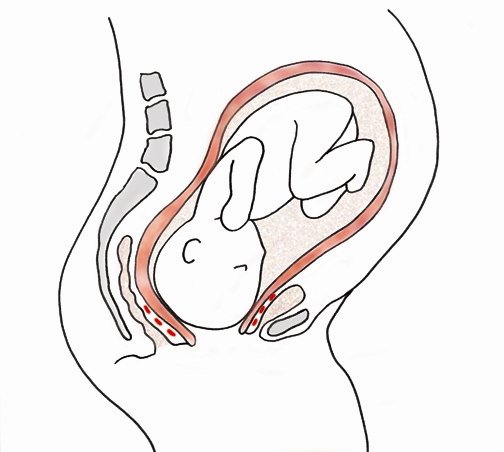

❖ Upper segment is hard, uniformly convex and tender. Lower segment is distended and tender.

❖ The pathological retraction ring is placed obliquely between the umbilicus and symphysis pubis and rises upwards in courses of time.

❖ Taut, tender round ligaments may be felt on either side,

❖ Foetal parts may not be well defined.